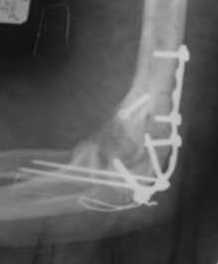

Подскажите пожалуйста, как можно в дальнейшем этому больному помочь. В марте первая

операция, пришлось оперировать на 16 сутки в виду инфицированных садин и анемии. Заживление

первичным натяжением, ранняя разработка после операции, а через 2 нед болевой синдром,и

постепенно движения в локтевом суставе ограничились до полного анкилоза. Повторно через 4

месяца вторая операция - артролиз, удаление оссификатов, удаление фиксаторов,

реостеосинтез этой же реконструкционной пластиной и винтом. Интраоперационно после

удаления оссификатов и фиксаторов обнаружил, что переломы не сросшиеся, поэтому пришлось

синтезировать заново. Зажила рана первично, объем движений в локтевом суставе сгибание 70,

разгибание160, ротационные движения востановились полностью, вроде бы успокоились.

Опять постепенно в течении 8 нед после повторной операции постепенно движения ограничились

до 80 - 110, на снимке оссификат. Снимки во вложении, буду рад Вашим советам. Спасибо!